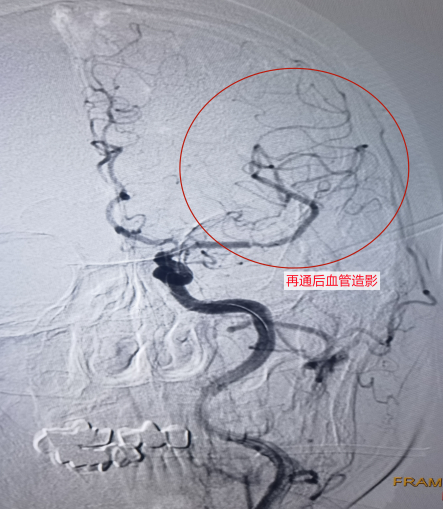

再通后造影

经过多科室共同的努力与紧密的合作,2小时后闭塞的血管成功被开通。

术后继续治疗与观察,王大爷能独立行走,完全恢复了原来的生活状态。

而王大爷的病情就是因为左侧大脑的主要动脉(称“大脑中动脉”)发生了急性闭塞,导致失语及右侧肢体出现完全性瘫痪等。